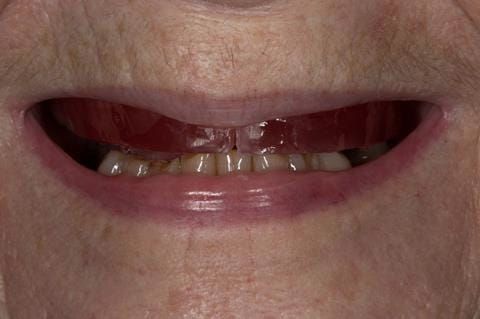

- Cobalt chromium reinforced gasket denture - using a Molloplast B "O" ring to retain and stabilise the denture. This was my professional preference as this was the least invasive and simplest solution to this dental problem. Should the UR7 require removal in the future - an artificial tooth could be added - resulting in a complete denture. The patient would have adapted to the denture fully by this stage and have good neuromuscular control of the prosthesis.

Following consultation and second discussion appointment the patient chose to have option 2 namely, a window denture - maxillary cobalt chromium based partial denture. The clinical situation and treatment process is shown in detail below with photographs. The patient was successfully rehabilitated with this and her quality of life considerably improved. The clinical work was provided by Finlay and the technical work by Rowan.